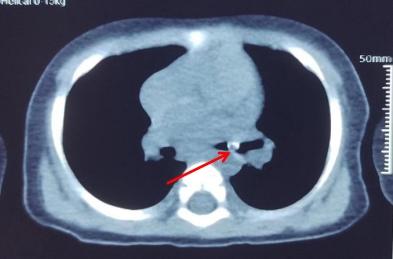

佛山市婦幼保健院在微信公眾號發文講述事件,指小周誤吞黃皮核後,家人初時覺得小周沒有甚麼異常,但後來小周日漸咳嗽、氣喘,多次看醫生都沒有明顯改善,直至去到佛山市婦幼保健院接受詳細檢查,才發現小周「氣管遠端-右主支氣管」有柱狀異物,並有「左肺肺炎」。

醫生分析,異物、即黃皮核落入氣管已有10天,不排除肉芽增生及黏膜炎症,加上黃皮核直徑大,極可能堵塞氣管開口,造成窒息、肺不張,甚至呼吸衰竭等危險,必須盡快做手術取出。